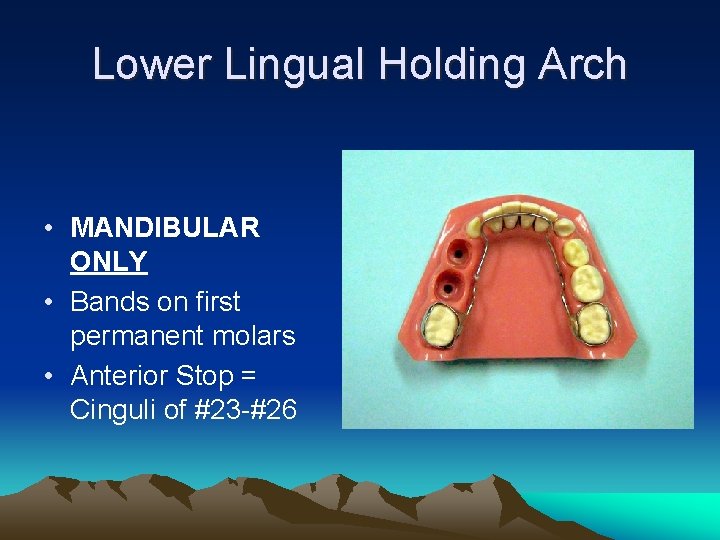

Lower Lingual Holding Arch • MANDIBULAR ONLY • Bands on first permanent molars • Anterior Stop = Cinguli of #23 -#26